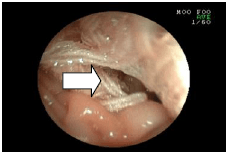

3. 胃のポリープを採ってきた例

![]() |

吐き気が続いている犬の胃の中を調べてみました。 大きなポリープが出来ていました。(矢印) |

ポリープがどんなものか調べるために、ポリープの一部をつまんで持ち帰ろうとしているところです。 検査の結果、このポリープは形質細胞腫(けいしつさいぼうしゅ)というガンだと分かりました。 |